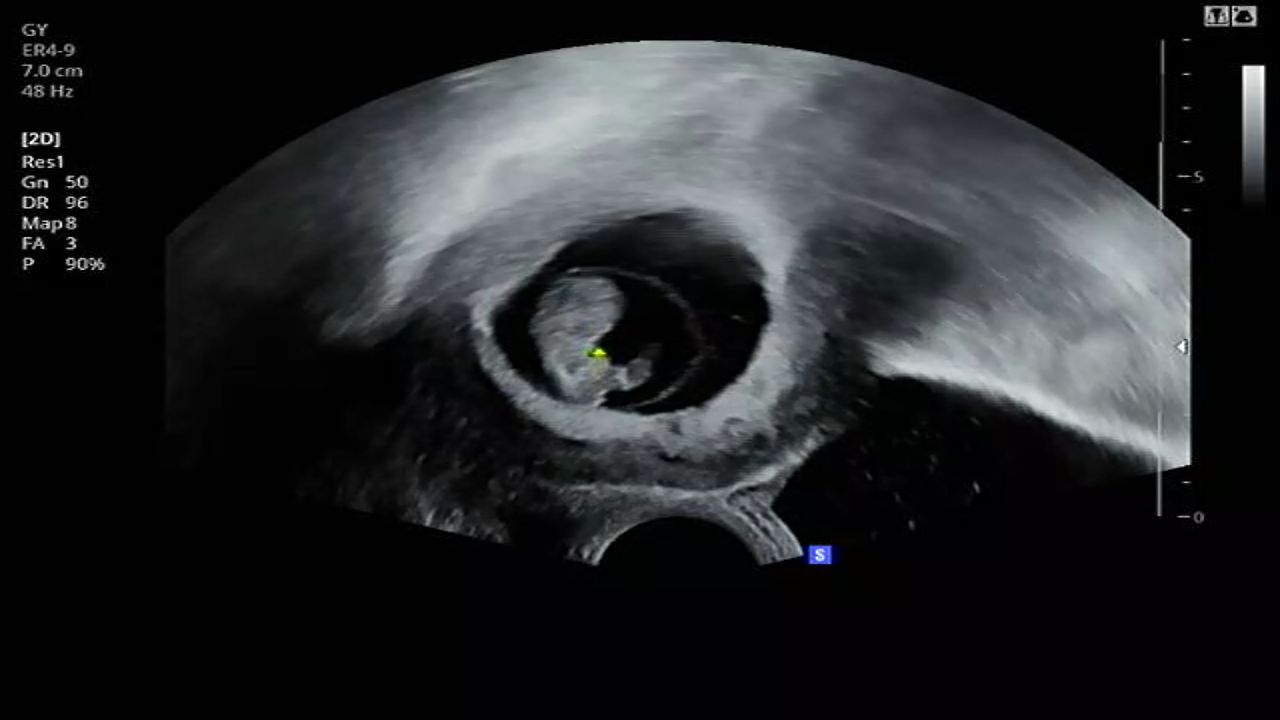

[11W5D] 정밀초음파와 1차 기형아검사.

12W에는 1차 기형아검사를 할 때 쯔음이라 주말에 맞춰 11W5D에 톨이와 함께 가연관악산부인과를 갔다.

꼬톨이는 너무도 건강하게 잘있었다 :)

아직 새끼손가락 크기밖에 되지않아 형태가 자세히 보이지는 않지만 꼬물거리는 모습, 팔과 다리 코까지 볼 수 있었다.

목둘레도 다행히 정상이고, 1차 기형아 검사인 듀얼코드검사(피검사)도 잘 마쳤다.

(목둘레가 정상수치를 넘어서면 다운증후군일 확률이 있다고 한다)